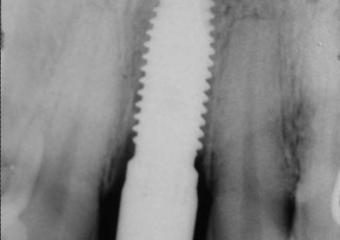

Raio X do implante instalado